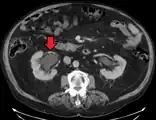

CT scan of bilateral hydronephrosis due to a bladder cancer

The choice of imaging depends on the clinical presentation (history, symptoms and examination findings). In the case of renal colic (one sided loin pain usually accompanied by a trace of blood in the urine) the initial investigation is usually a spiral or helical CT scan. This has the advantage of showing whether there is any obstruction of flow of urine causing hydronephrosis as well as demonstrating the function of the other kidney. Many stones are not visible on plain X-ray or IVU but 99% of stones are visible on CT and therefore CT is becoming a common choice of initial investigation. CT is not used, however, when there is a reason to avoid radiation exposure, e.g. in pregnancy.[13][14]